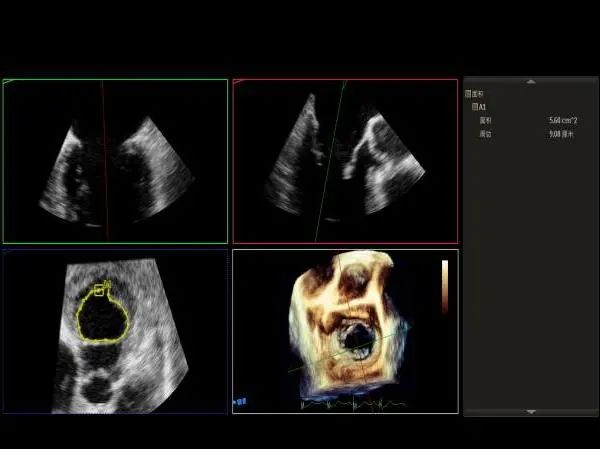

Qlab软件勾画估测瓣口面积约:5.6cm²

3D视图下观察二尖瓣双孔形态

3D-color:残余少量返流